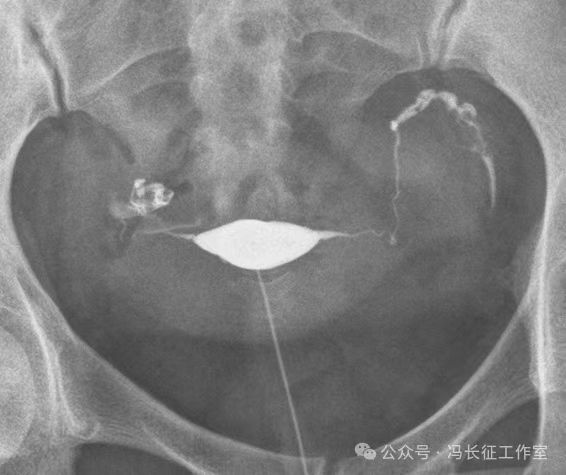

下面是一例正常子宫输卵管造影图(4张片)

微信图片_20240215160211.jpg